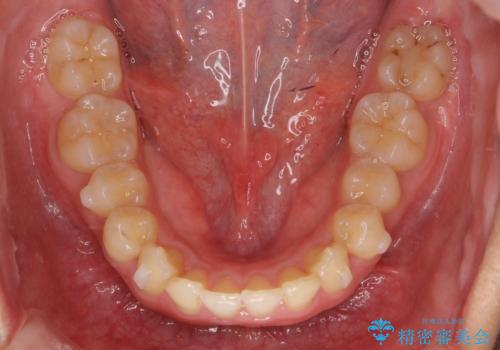

- 前歯の前突を主訴に来院。

かみ合わせが深く、また奥歯のかみ合わせも全体的に上が前にずれていました。

抜歯矯正も難しく、非抜歯矯正も歯の移動量が多くいずれにしても難易度が高い状態でした。

時間はかかりますが非抜歯で治療することにして、インビザライン矯正とワイヤー矯正を交互に行い仕上げました。

インビザライン矯正だけでなく、途中ワイヤー矯正もはさみました。前歯のかみ合わせが深く、本当に大変な治療でしたが協力度も高く非抜歯で上の奥歯を後ろに動かすことができました。